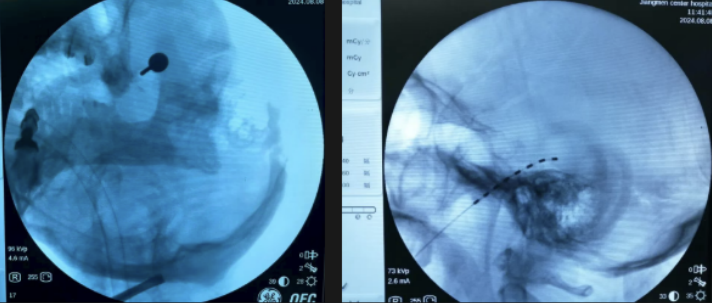

2.三叉神经半月节微球囊压迫术

三叉神经痛素有“天下第一痛”之称。经皮三叉神经半月节微球囊压迫术是一种微创治疗技术,无需开颅,通过穿刺将微球囊置入三叉神经半月节区域,短暂压迫以阻断异常痛觉传导,具有创伤小、风险低、起效快、疗效确切、疼痛缓解维持时间长等优势,现已成为治疗顽固性三叉神经痛患者的首选治疗方案之一。

我院疼痛科自2022年开展此项技术以来,已成功为近百例患者实施手术,临床效果显著,术后疼痛缓解率高,且无一例发生严重并发症。

△三叉神经半月节微球囊压迫术